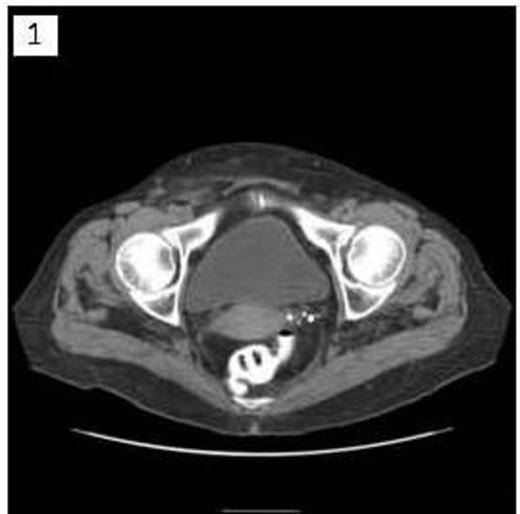

A 68 year old female presented to clinic with a several year history of right lower quadrant abdominal discomfort and “bulge”. Physical exam demonstrated a reducible mass originating in the inguinal region that tracked cephalad above the level of the inguinal ligament. CT imaging revealed a large inguinal hernia defect (Figure 1) with herniated bowel coursing 13cm cephalad between the external and internal abdominal oblique muscles (Figure 2 & 3).